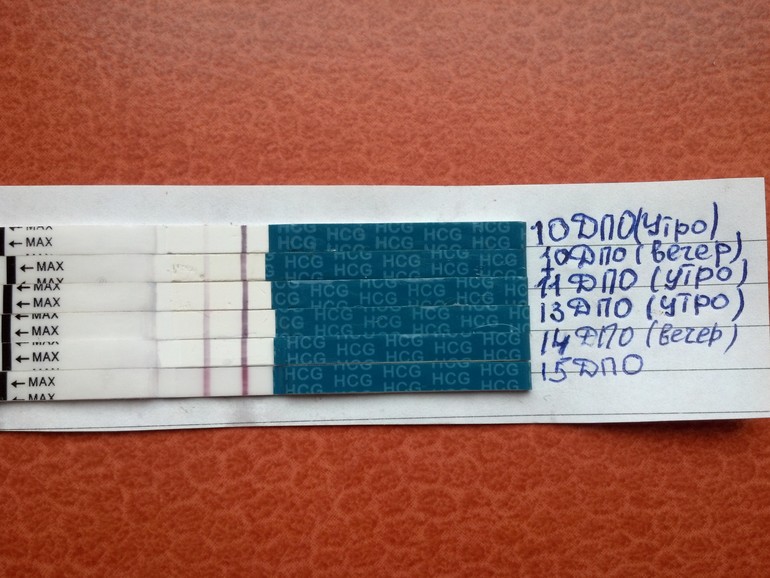

с каждым днем полосочка ярчала